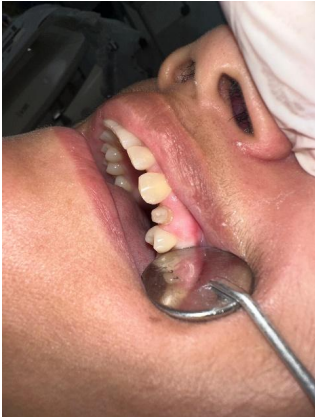

1ª Sessão: Inicialmente foi realizado a desubturação parcial dos canais radiculares, mantendo o selamento apical com o comprimento mínimo para garantir o sucesso endodôntico. Em seguida, foi realizada a prova e ajuste do pino de fibra de vidro, o qual apresentou boa adaptação, dessa forma, foi feita a anatomização dos condultos e cimentado com cimento resinoso dual, considerando o protocolo adesivo adequado: condicionamento ácido, aplicação dos adesivos compatíveis e inserção do cimento nos canais, garantindo o preenchimento adequado e ausência de bolhas, após essa etapa, foi realizada a fotoativação e fotopolimerização completa, o núcleo coronário foi preenchido com resina composta para criar um remanescente anatômico que possibilitasse a confecção do preparo. Na sequência foi realizado o preparo para receber a coroa total, respeitando os princípios da retenção, resistência e espessura do material. Para a moldagem funcional a gengiva foi afastada com o fio retrator, e executada com silicona de condensação (pesada e leve), garantindo a cópia fiel dos limites cervicais. Posteriormente foi confecciada uma coroa provisória em resina composta, devidamente com a oclusão ajustada e protocolos de polimento, proporcionando conforto, e estética satisfatória à paciente. A cor foi escolhida e o molde juntamente com o registro de mordida foram encaminhados ao laboratório para que fosse confeccionada a coroa de teste clínico, e na sequência a coroa definitiva.

Figura – Inserção dos pinos de fibra de vidro